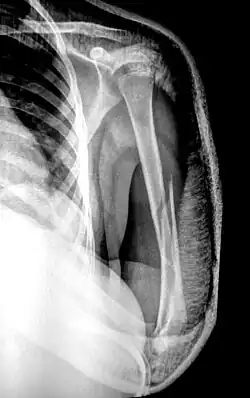

There are two main categories of fracture reductions: closed reductions and open reductions. Both procedures require confirmatory imaging – such as X-ray – both before the reduction to confirm the misalignment of bones and after the reduction procedure to confirm successful achievement of anatomical positioning.

Dislocation reduction

Reductions for dislocations are dependent on the joint they involve. Common dislocations include the shoulder, finger, hip, knee and patella. In children, the elbow is also a common dislocation and referred to as nursemaid's elbow. There are many techniques but the same tenets are generally applied to all dislocation reductions. Traction, or sustained pulling pressure, is applied to the distal bone of the dislocated joint to relax the surrounding musculature and create space for the bone to move back into anatomical position.[11] Traction can be applied either by human strength or with a system of pulleys and weights. Surrounding muscles, nerves and vasculature can be disrupted during the initial injury which can result in further surgical requirements even if proper bone alignment is achieved.